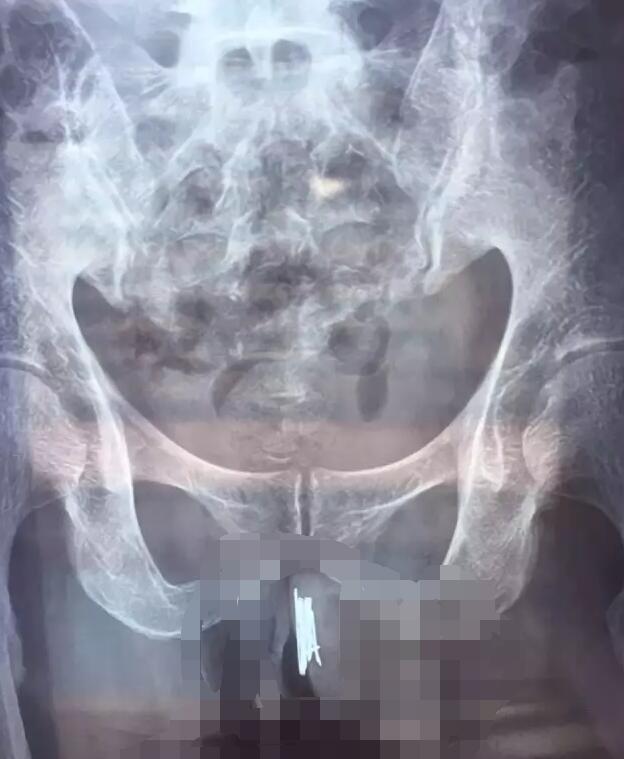

排尿痛苦并伴有血尿!11岁男童尿道内惊现17颗磁力珠近日,一名11岁男童突发血尿,经检查竟在其膀胱及后尿道发现17颗磁力钢珠,江西省儿童医院泌尿外科副主任医师唐静治疗团队顺利为其取出。目前,男童正在康复中。 3天前,来自江西南昌的11岁男童小磊(化名)偷偷地把玩一些磁性材质的小珠子,珠子直径均约5mm,因磁吸力较强,相互靠...